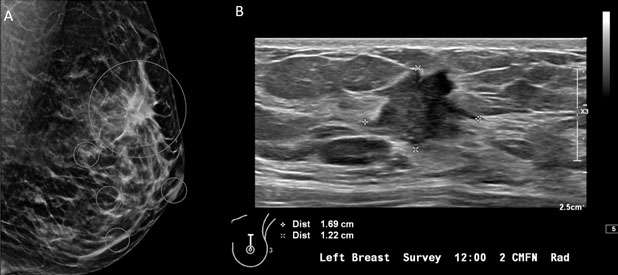

3. Irregular: the shape of the mass is neither round nor oval (Figure 3).

Mammography: Masses Figure 3

Figure 3: A) Mammography of the left breast with MLO view demonstrates irregular, spiculated mass in the left breast at 12 o'clock (big white circle). Additional calcifications in the left breast at 8 o'clock at anterior depth located 2 centimeters from the nipple, three additional groups of calcifications in the central and lower inner left breast are also suspicious (small white circles). B) Ultrasound of the left breast represents an irregular, spiculated hypoechoic mass, BI-RADS Category: 4C suspicious finding. Ultrasound guided biopsy was recommended and confirmed invasive ductal carcinoma, grade 2.